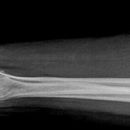

Unterarm total ventro-dorsal (1. Ebene a.-p.)

Fraktur, Stellungskontrolle, Osteosynthesematerial

Ulnar und Radius dürfen sich nicht überkreuzen (bei prox. UA). Ein Gelenk muss immer mit abgebildet sein.